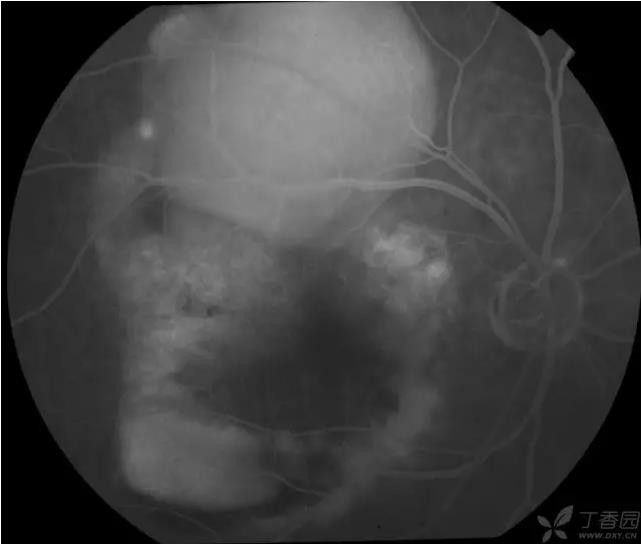

▼颞上分支静脉阻塞

实用贴:眼科病例高清图片